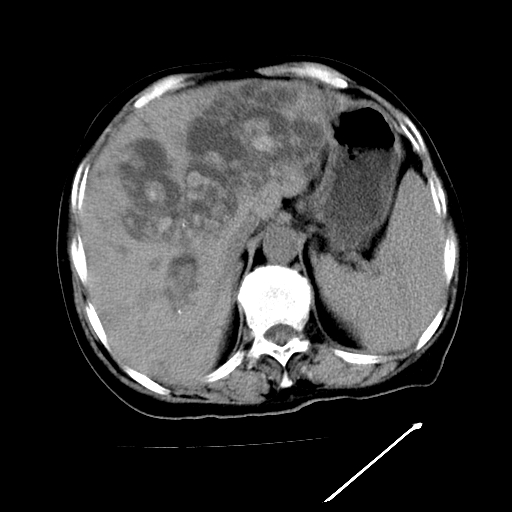

以下是引用随光逐影在2009-4-7 8:21:00的发言:[br]肝内外胆管多发性结石并肝内外胆管扩张;胆系感染。